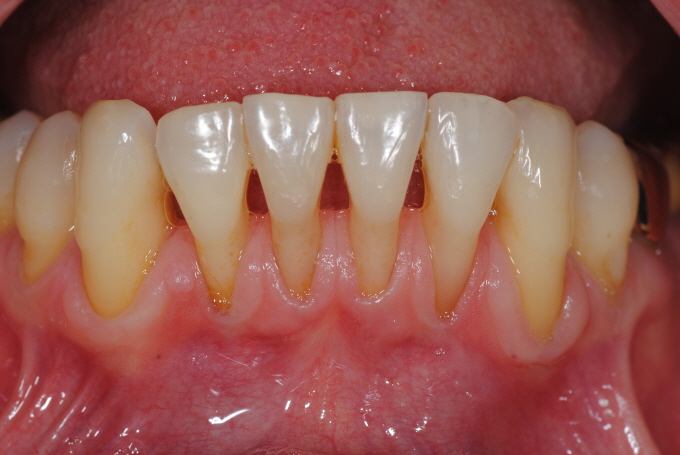

| Fig. 1: 56¼¼ ¿©ÀÚ, ¼øÂ÷Àû Ä¡ÁÖÄ¡·á¿Í ¼ö¼ú ±×¸®°í ±³Á¤Ä¡·á µî Àå±â°£ÀÇ Ä¡·á ³¡¿¡ ¾ÈÁ¤µÈ ±³ÇÕ¿¡ °í¸¥ Ä¡¾Æ¹è¿À» ´Þ¼ºÇÏ¿´°í ´ÙÀ½ ´Þ Áß¼ø°æ ÇÏ¾Ç ÀüÄ¡ºÎÀ§¿¡ ´ëÇÏ¿© BiotypeÀÇ °³¼± ¹× Ä¡±Ù Çǰ³¸¦ À§ÇÑ Mucogingival Plastic Surgery¸¦ ¿¹Á¤Çϰí ÀÖ´Ù. |